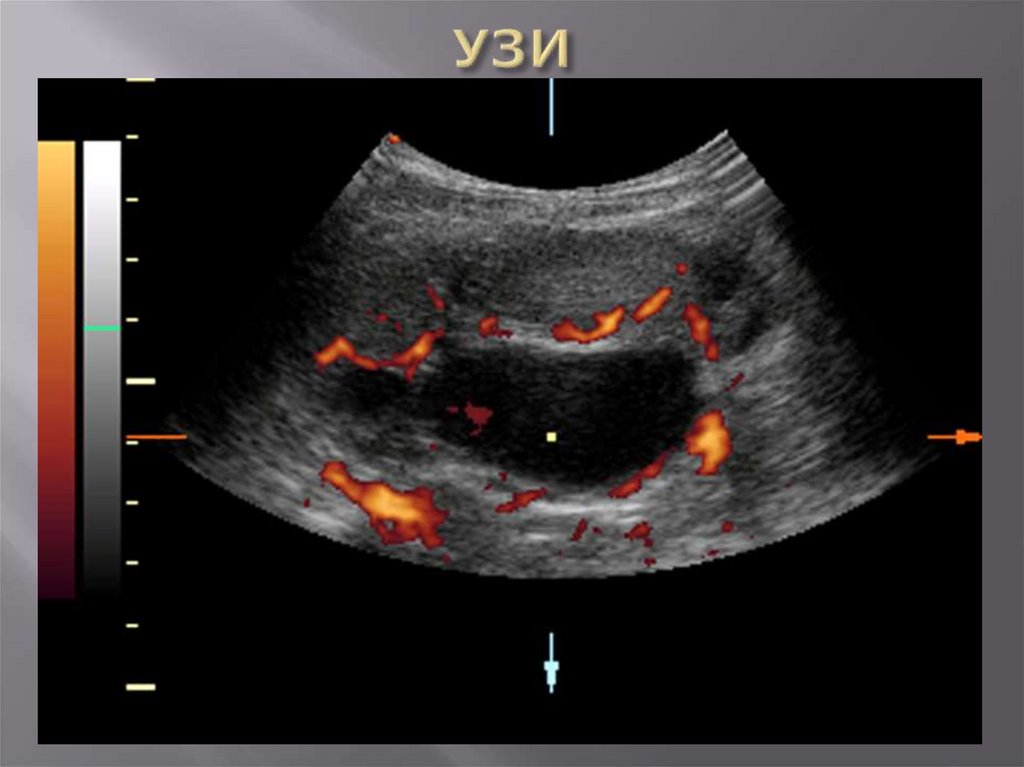

Осмотр органов мочевой системы

Органы мошонки

Допплерография сосудов почки, яичка

Определение размеров лоханки,

мочеточника, состояния паренхимы

почки